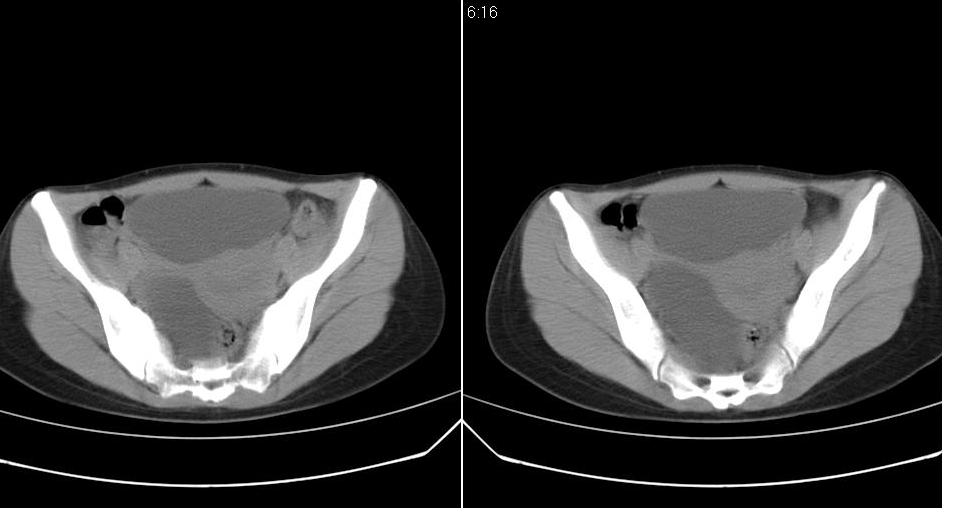

标题: CT22811:女 36岁,B超提示右侧附件囊性占位。 [打印本页]

标题: CT22811:女 36岁,B超提示右侧附件囊性占位。

先考虑---卵巢囊肿。

子宫内膜增厚---可能是卵巢激素紊乱造成的。

右侧卵巢囊肿

右侧卵巢囊肿。

支持右侧附件良性囊性占位性改变。

手术结果证实为右侧输卵管囊肿。

输卵管囊肿罕见,从影像上无法同卵巢囊肿区分。

输卵管囊肿一般是指输卵管受病原体感染以后,由于白细胞的浸润形成内膜肿胀、间质水肿、渗出,输卵管粘膜上皮脱落,如果输卵管急性期炎症没得到及时有效的治疗就形成了输卵管积脓。输卵管积脓在炎症消退后,脓液逐渐被吸收,腔内积液由脓性变为浆液性,则成为输卵管囊肿。

还是报右侧附件区良性囊性占位性改变       至于输尿管或卵巢囊肿不太好鉴别